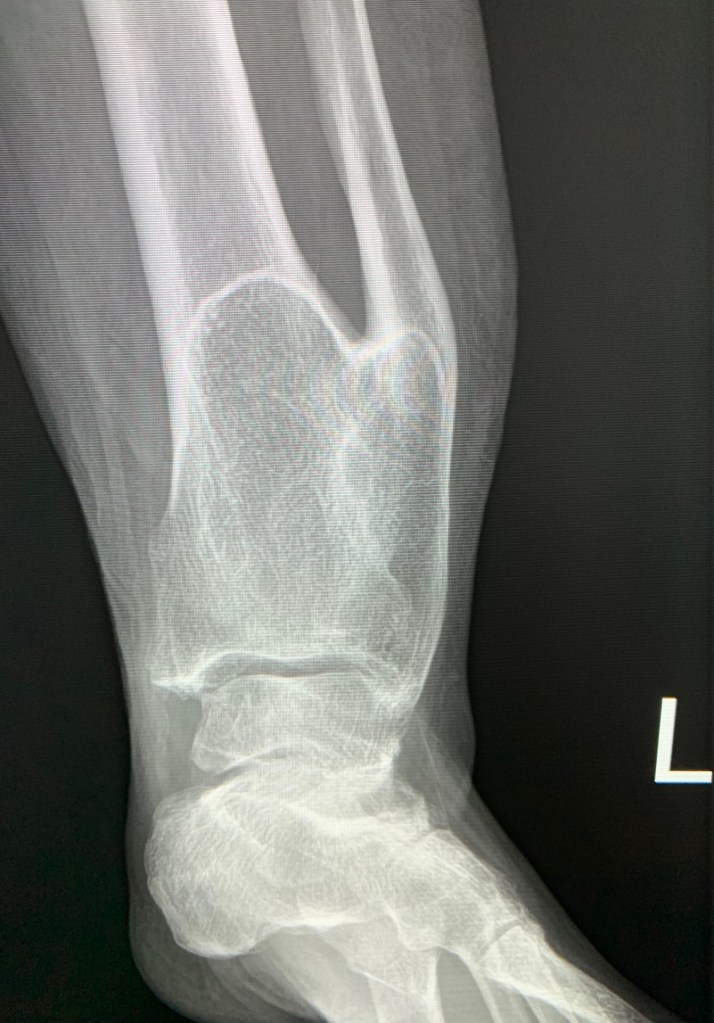

Axial CT image through the proximal penis with surrounding scrotal edema. The mouth is the urethra within the corpus spongiosum. The eyes are the cavernosal arteries within the paired corpora cavernosa.